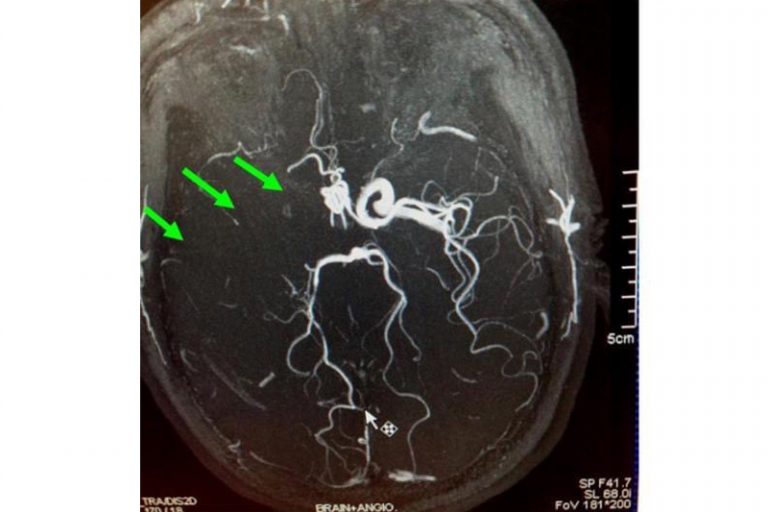

圖:右邊頸和腦部血管大動脈全部都被血栓堵塞着。

羅先生被送往私家醫院的第一步是進行緊急磁力共振造影,報告顯示羅先生右邊頸和腦部血管大動脈全部都被血栓堵塞着,右邊大腦缺血水腫,導致左邊手腳冇力和神智半昏迷。經過腦血管外科醫生的診斷和急救,在全身麻醉下,醫生使用尤如髪絲微細的導管,經過病人右邊大腿的腹股溝的大動脈而入,導管再經過腹部和胸腔的大動脈一直向上,遊走到病人右邊的頸和腦部血管大動脈,進行機械式血栓吸取內血管治療急救。